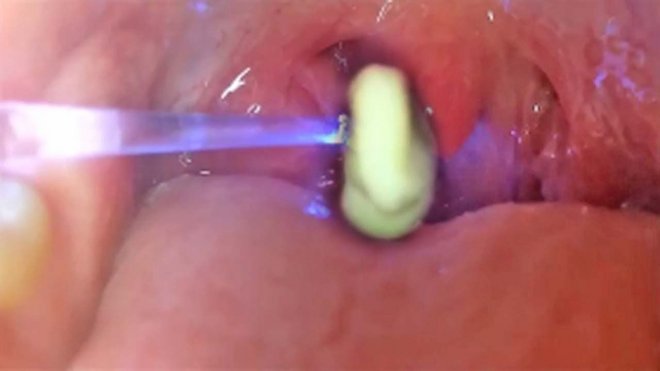

扁桃腺結石致口臭、喉嚨痛扁桃腺是喉嚨後兩側的腺體,充滿罅隙,當扁桃腺反覆發炎便會造成罅隙的小窩加深,食物殘渣或細菌容易卡在小窩中,2至3日之後與唾液及細菌混合,變成扁桃腺結石。結石會發出惡臭,令患者有口氣問題,甚至會喉嚨嚴重發炎,連吞嚥口水也痛。如果嚴重或致頭痛、耳朵痛癢、嘔吐等情形,建議直接去找耳鼻喉科醫生。

嚴重需開刀清除台灣媒體近日亦有就此進行報導。高雄長庚醫院耳鼻喉科主治醫師羅盛典表示,曾經某些患者有不只一顆結石,因患者扁桃腺位置的隱窩為「外窄內寬」構造,藏了多達10幾顆結石,需立即開刀摘除扁桃腺。另有耳鼻喉科專科醫生指,如果依網上流傳用牙籤或棉花自行剔走結石,有可能誤傷扁桃腺,導致反覆發炎,故建議患者先求診較好。